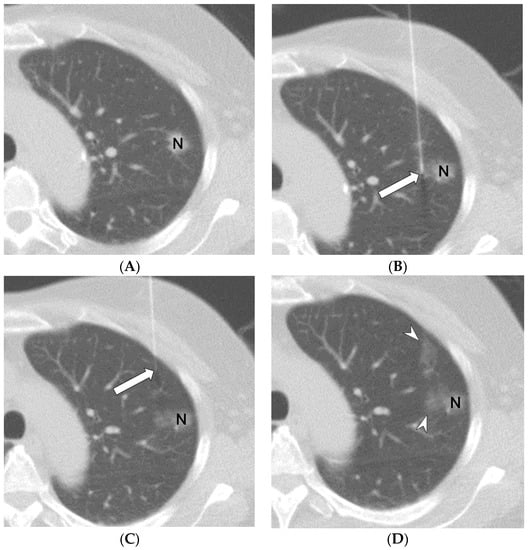

2.2. Methods for CT-Guided Localization with PBV Dye